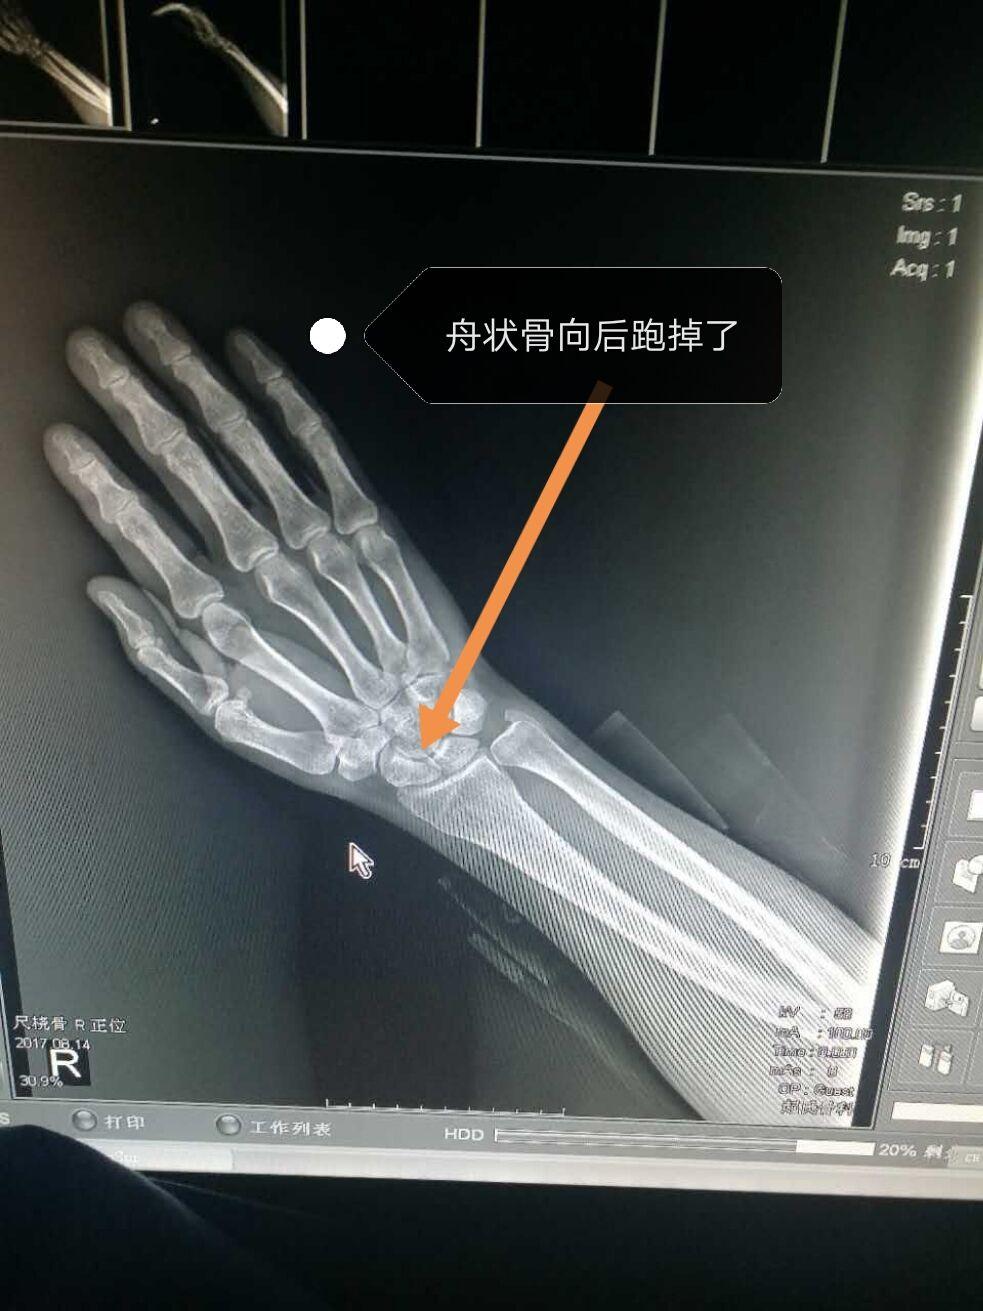

手骨头凸起

图片尺寸540x960

手腕骨头坐自行车摔倒,双手手掌心落地,经过两个多月自然恢复发觉手腕

图片尺寸1000x563